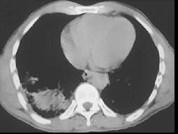

男,31岁,车祸后10小时余,请结合影像学检查,选出最可能的诊断 ( )A.肺癌B.肺结核C.气胸伴肺挫伤D.硅沉着病E.大叶性肺炎

问题 男,31岁,车祸后10小时余,请结合影像学检查,选出最可能的诊断 ( )

选项 A.肺癌 B.肺结核 C.气胸伴肺挫伤 D.硅沉着病 E.大叶性肺炎

答案 C